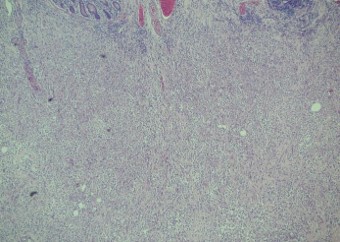

Pathology of the right hemicolectomy specimen was “involvement by metastatic carcinoma, immunoprofile compatible with breast primary”. The cytokeratin profile was CK7+, GATA3+ and MOC-31+, and negative for CK20 and CDX-2. There was very focal positivity for E-cadherin, while p120 catenin mostly showed cytoplasmic staining in the tumour cells. Microscopic examination suggested that the tumour invaded from mucosal side of the intestinal towards the serosa; the proximal and distal resection margins were clear. The morphology and immunoprofile point towards a metastatic carcinoma of breast.